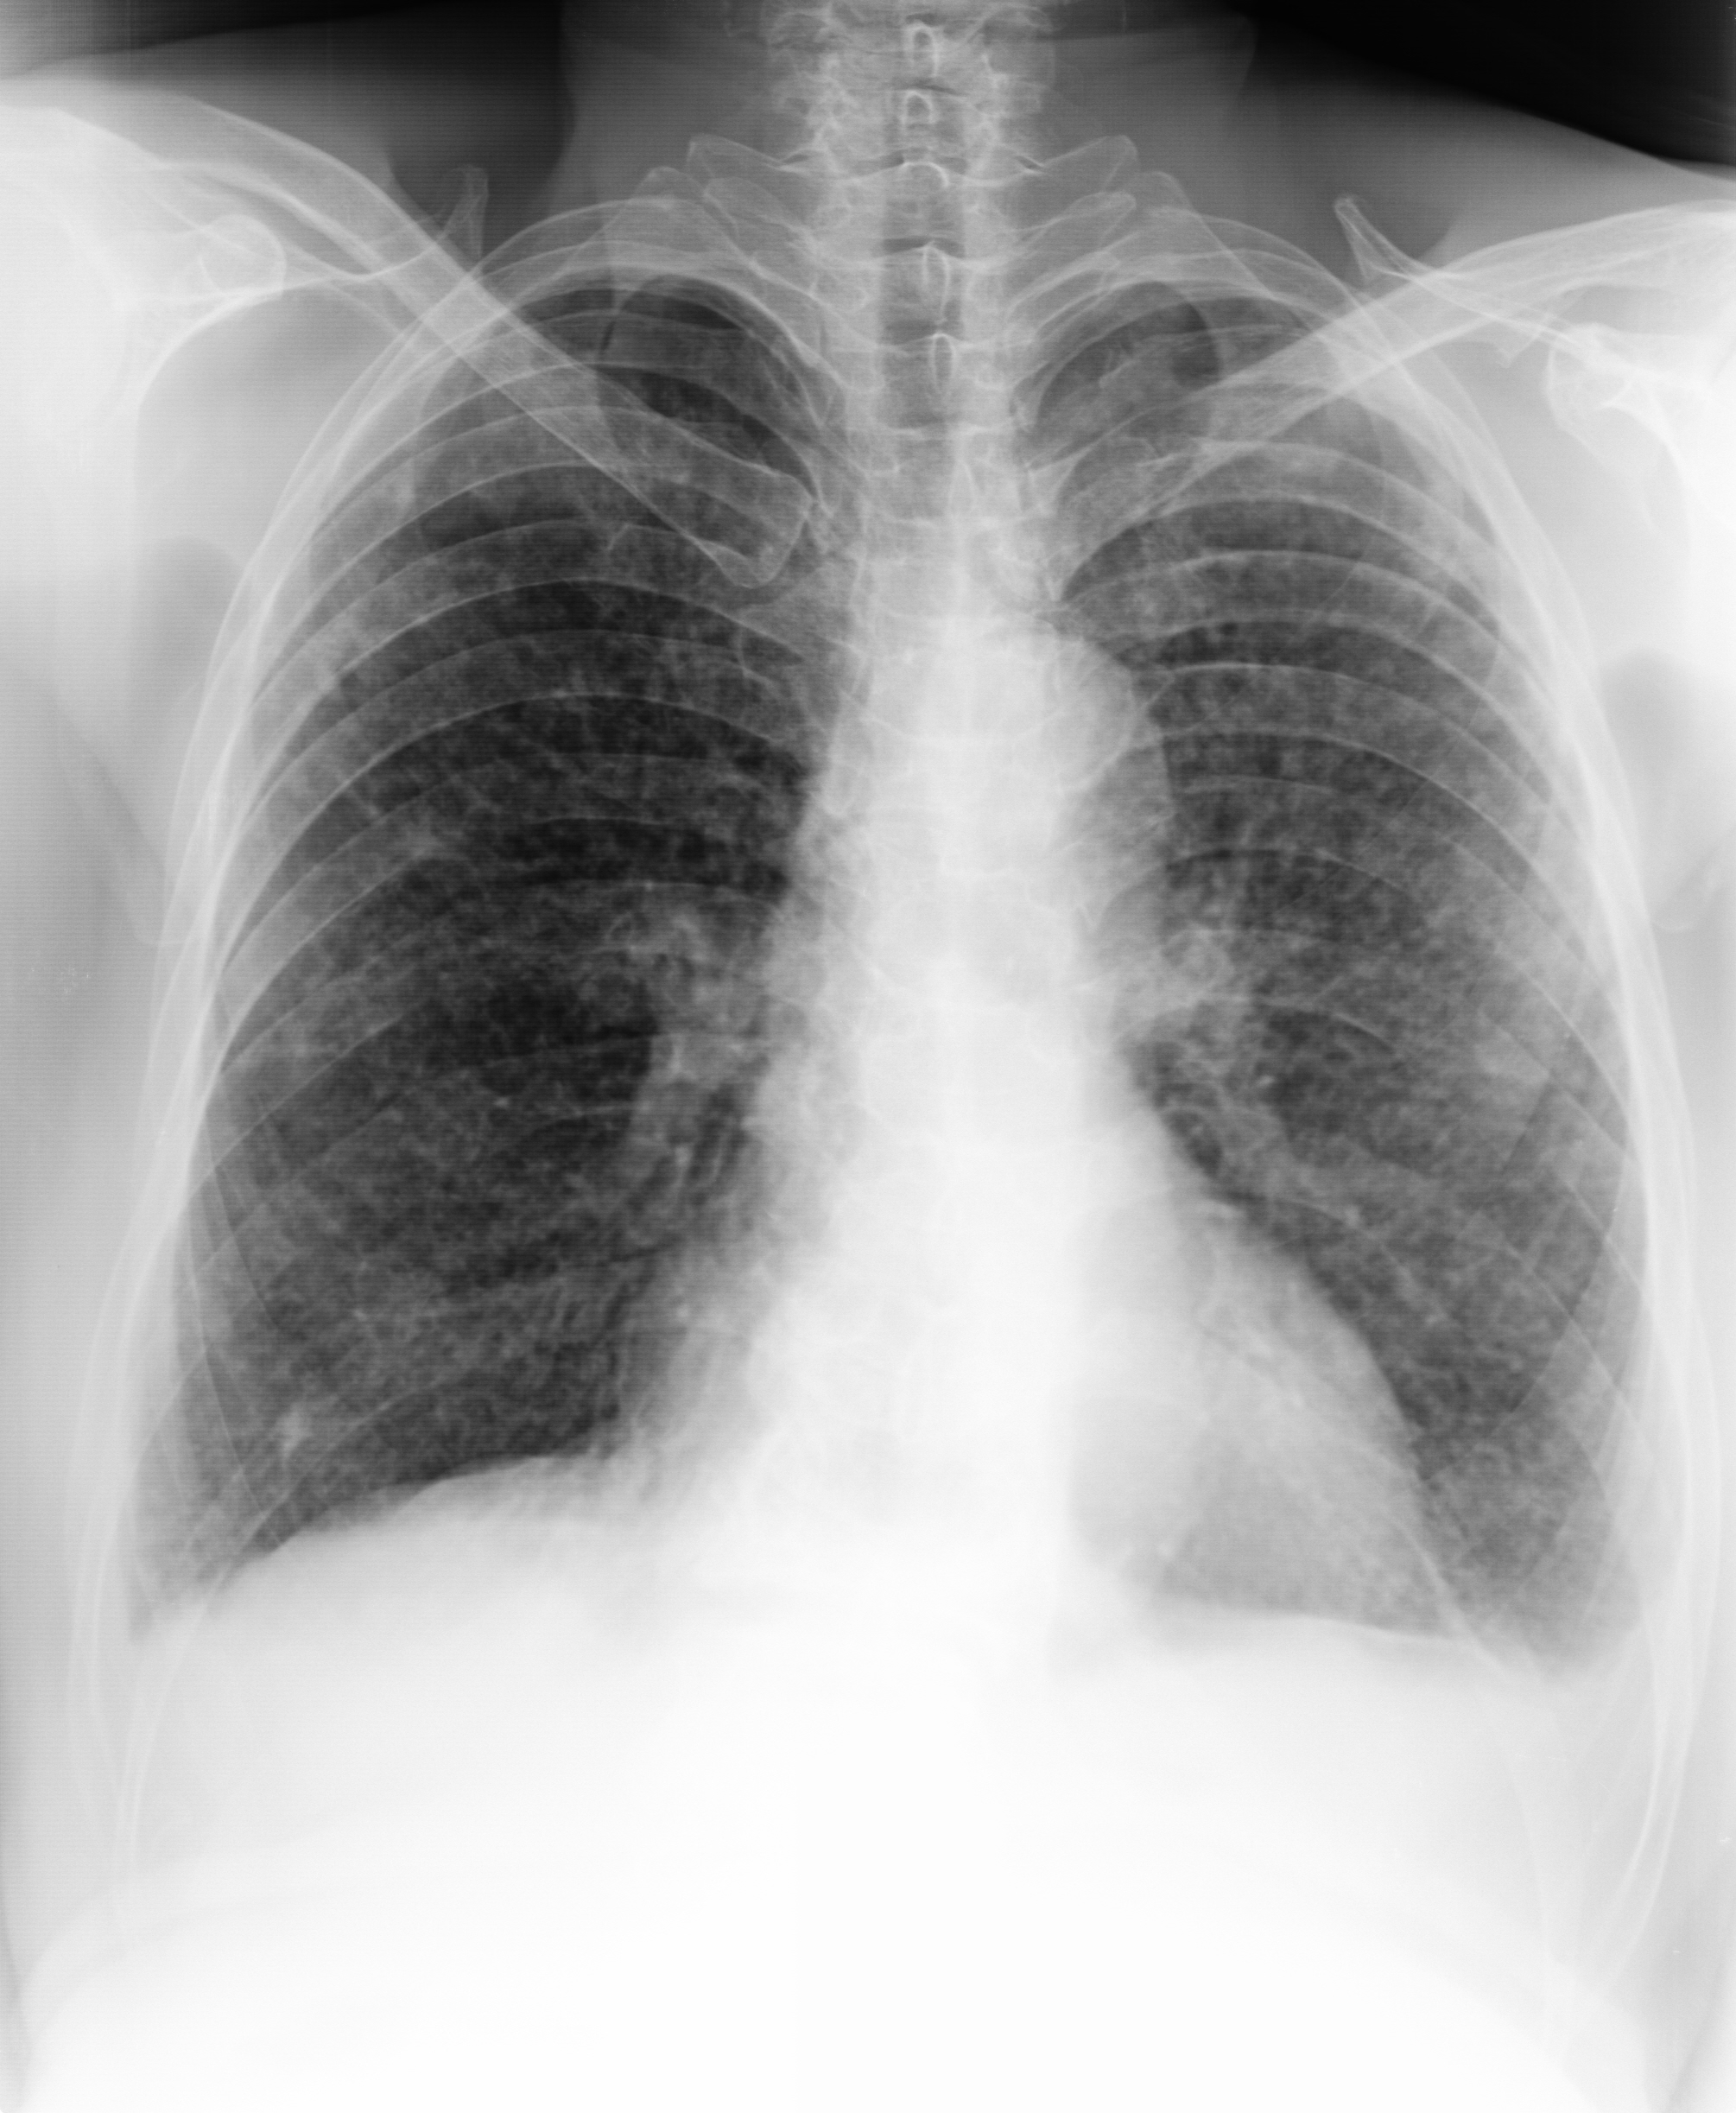

X14170:胸片 男 84岁

咳嗽 发热。白细胞增高。大家帮忙看看像什么?考虑结核吗?怎么写报告?

两肺纹理模糊,两肺内可见弥漫粟粒结节,右肺少许散在钙化,左侧肋膈角闭塞。右肺透光度稍增加。考虑:两肺粟粒性结核可能。左侧胸腔积液。建议CT检查。

两肺野见分布均匀,大小、密度一致粟粒状阴影;肺纹理被掩盖;左肋膈角消失。两侧肺门未见增大、增浓;双膈面光整,心影大小、形态正常,主动脉未见异常; 纵隔居中、无增大;两侧胸廓对称,无畸形;其它:未见异常

意见:两肺急性粟粒型肺结核。

左侧胸腔积液。

两肺弥漫分布粟粒样结节阴影,密度均匀,以左肺较密集,部分融合,左肋膈角消失。

心影、纵膈未见明显异常。影像:血性播撒型肺结核。

支持粟栗状结核伴左侧少量胸腔积液

结合临床症状典型。年纪较大,不排除转移性病变。